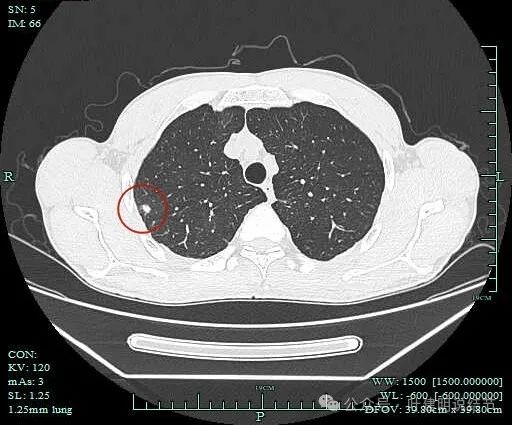

病灶2:

影像截图:

病灶出现,密度杂乱。

有磨玻璃成分,且轮廓清,磨玻璃边缘有细毛刺征,实性成分的边缘毛糙不平,形态不规则。

灶内有僵硬支气管走行,边上少许磨玻璃成分,病灶有一定收缩力。

灶内支气管穿行且显得僵硬。

胸膜牵拉,灶内支气管通气征并显僵硬,部分边缘有毛刺征。

有血管进入并异常增粗;病灶有分叶征,有毛刺征,也有胸膜牵拉征。

病灶有细毛刺征,感觉有收缩力。

实性成分为主,边上少许磨玻璃成分。

叶间胸膜牵拉。

病灶2影像印象:

这个病灶是非常典型的恶性的,总体上基本上是实性成分,但边上仍有少许磨玻璃,而磨玻璃成分有分叶与细毛刺,病灶内部有支气管通气征,且支气管显僵硬,又有异常增粗的血管进入。再加上胸膜牵拉、叶间裂牵拉,整体轮廓较清,周围肺野清爽,没有卫星灶。所以基本上就是浸润性癌了的。